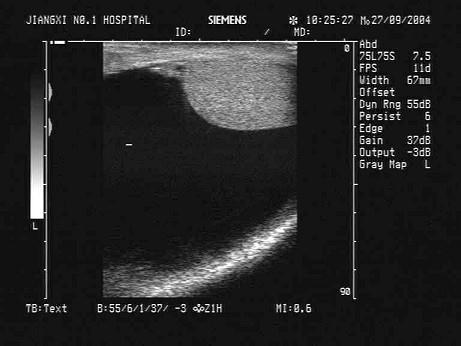

问题 根据超声声像图,最可能的诊断为?(?)

选项 A.睾丸鞘膜积液 B.精索鞘膜积液 C.阴囊壁水肿 D.肠疝 E.睾丸精索鞘膜积液

答案 A